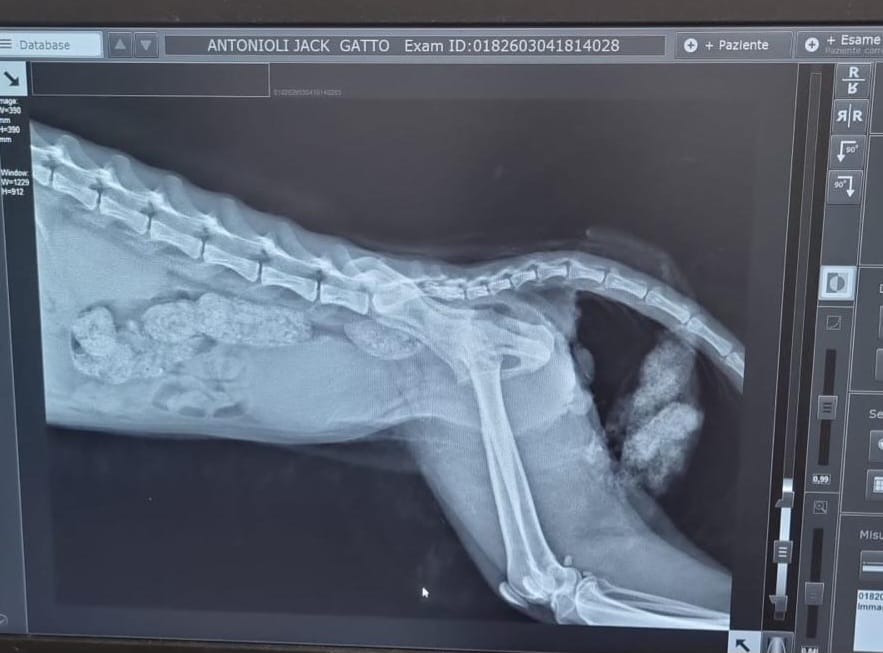

Jack è un gattino FeLV positivo che pochi giorni fa ha perso all’improvviso l’uso del treno posteriore. La radiografia mostra un’ombra sull’ultima vertebra: potrebbe essere un tumore o un coagulo causato da una caduta. L’unico modo per capirlo è una risonanza magnetica urgente.